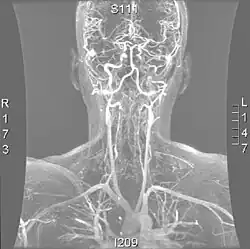

Arteries of the neck, with arrows indicating the right vertebral artery | |